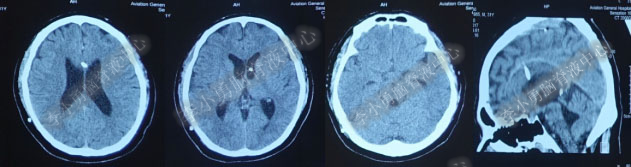

术后7天(2016年5月18日),症状有所缓解,复查头部MRI(图-2)幕上脑室较术前缩小,但是“四脑室仍扩张”,医生认为 “正常”于术后8天(2016年5月19日)出院。

图-2:2016年5月18日头部MRI

图-3:2016年9月26日头部MRI

第1次内镜术后330余天即11个月(2017年4月),又开始出现头晕症状并逐渐加重。2017年6月13日(第1次内镜术后367天),行头部MRI(图-4)检查显示全脑室系统扩大。

图-4:2017年6月13日头部MRI